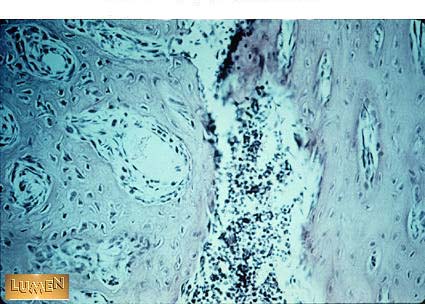

What kind of bone is this?

Spongy